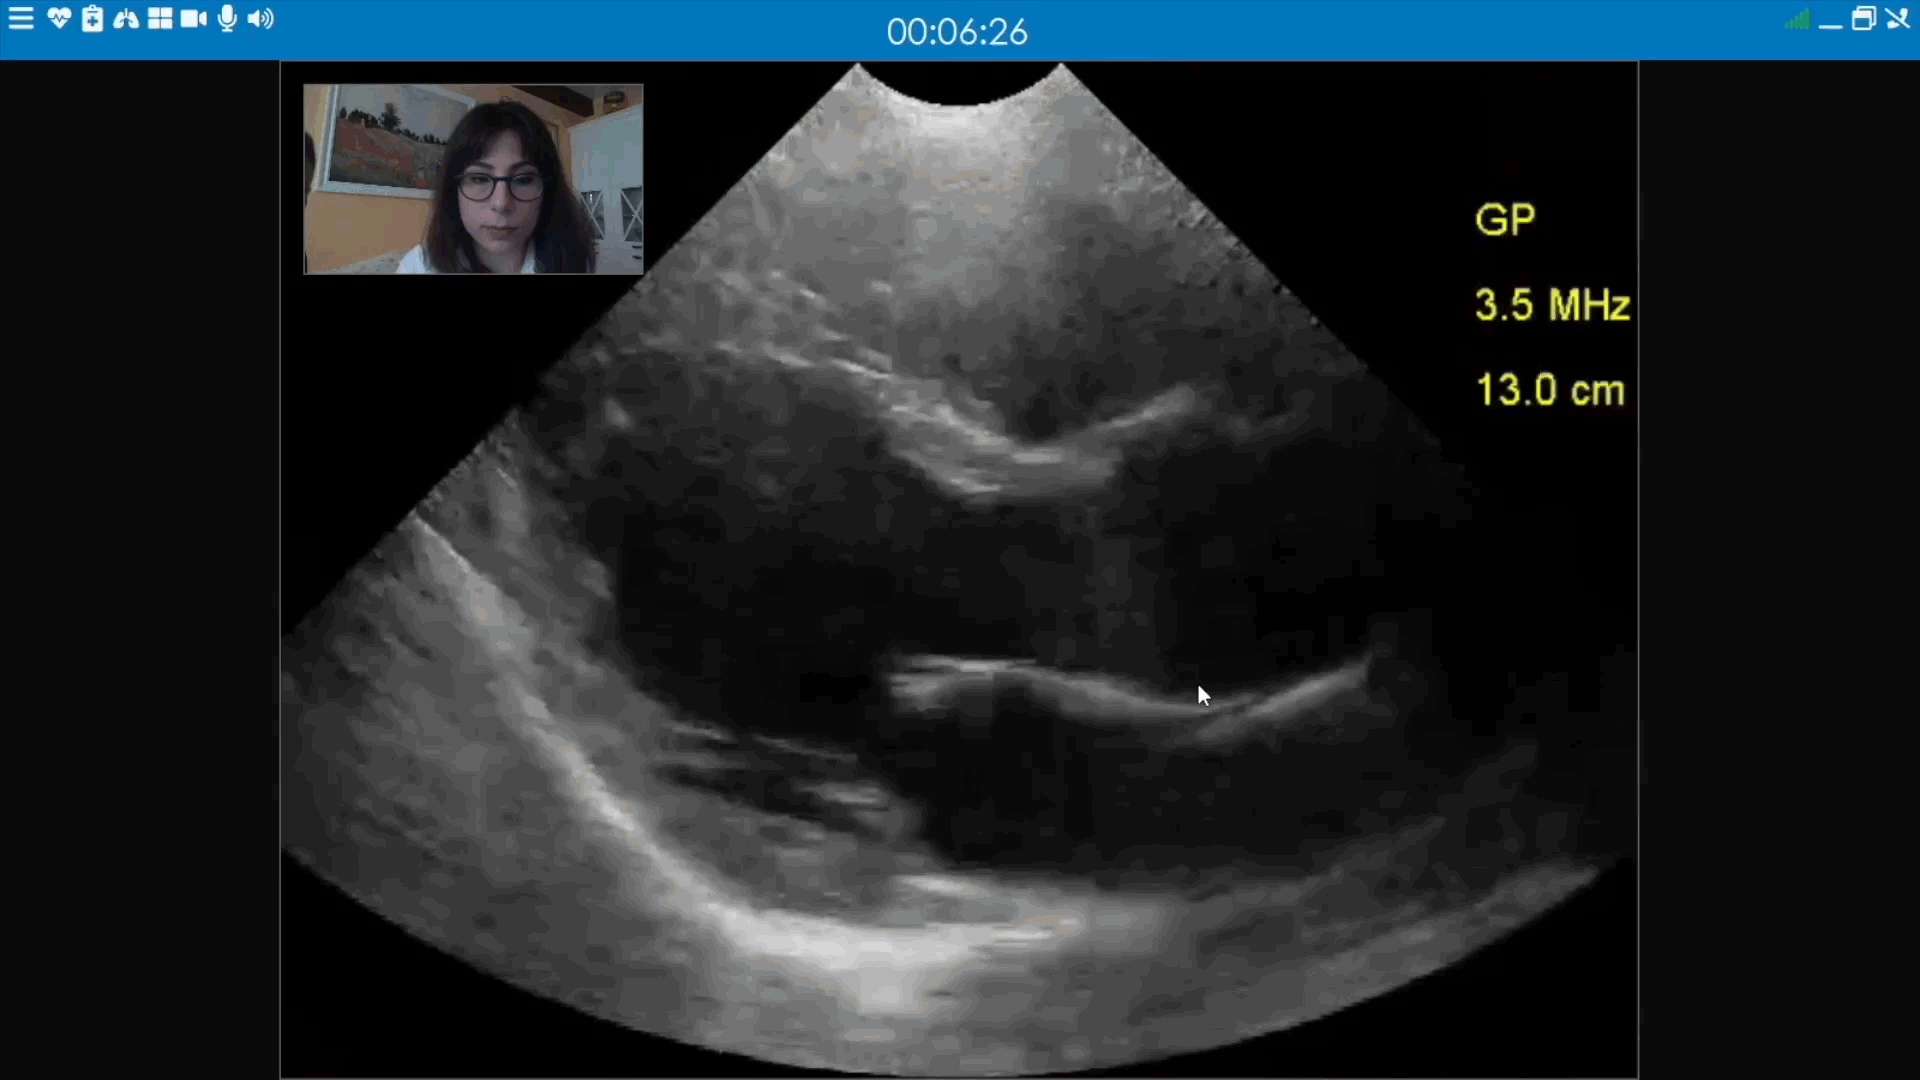

Integrate your Smart Ambulance with plug-and-play medical peripheral devices to provide remote clinicians with access to real-time patient examinations.

Ultrasound